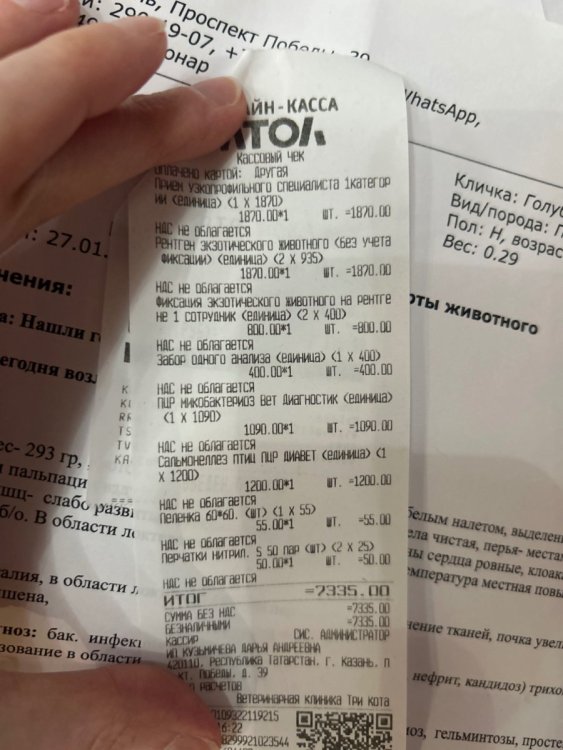

@свс у нас брали помет на анализ, но не включили его в стоимость, так как «там ничего такого, бактерии как и у всех уличных». Спасибо на этом 😂 и дополнительно взяли анализы на сальмонеллез и микобактериоз (анализов еще нет) честно немого в шоке с неправильных доз, потому что мы именно к ней всегда ездим и по ее дозам лечимся Это вот что мы делали микроскопия кала не включена но сделана пошла фоткать все что вы написали